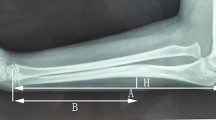

The Picture Archiving and Communication System (PACS) version used was AnnetPACS V 2.0.01. All imaging data were independently measured by a senior orthopedic resident who had undergone three months of systematic radiology training. To ensure the reliability of the measurement data, ten X-ray films were randomly selected and measured by both a senior associate chief orthopedic doctor and an attending doctor from the imaging department to authenticate the measurements. Three researchers used identical computer programs with consistent measurement software. The inner-epiphyseal ulna length (IEUL) was defined as the distance from the tip of the olecranon to the midpoint of the distal epiphyseal plate of the ulna (red line). The inner-epiphyseal radial length (IERL), represented by the yellow line in Fig. 1, was defined as the distance between the midpoints of the radial head epiphysis and the distal radius epiphysis. The inner-epiphyseal ulna-radius length ratio was calculated as follows:

A total of 432 children aged 1–15 years with ulna and radius X-ray films were included, with a minimum of 30 children in each age group. There were 255 boys (59.0%) and 177 girls (41.0%). The left forearm was measured in 236 children (54.6%), while the right forearm was measured in 196 children (45.4%). The mean inner-epiphyseal ulna-radius length ratio was 1.094, with a standard deviation of 0.024, and the range of values was 1.0336 to 1.168. The 95% medical reference range was 1.047 to 1.141, both the ulna and radius lengths increased with age, their length ratio at the epiphyseal plate remained relatively constant across age groups (Fig. 2).

We found that while both the ulna and radius lengths increased with age, their length ratio at the epiphyseal plate remained relatively constant across age groups (Fig. 2). In our study of acute Monteggia fractures in children, immediate restoration of the normal inner-epiphyseal ulna-radius ratio during surgery resulted in favorable elbow joint function outcomes and radiographic scores. In the pediatric chronic Monteggia fracture group, patients who achieved restoration of the radius-to-ulna ratio between 1.014 and 1.147 during surgery exhibited improved elbow function, joint range of motion, and radiographic scores. In contrast, inadequate restoration of this ratio resulted in poor elbow function and radiographic scores, leading to suboptimal treatment outcomes. Therefore, when performing ulna lengthening for forearm fractures, it is crucial to restore both ulna and radius lengths to the normal range through careful preoperative planning.